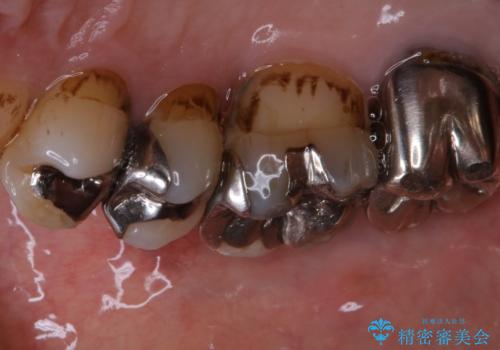

施術後の歯の表面に、茶色く色が残っている所がありますが、これは詰め物の変色の所と、虫歯になっている所です。以前に、CR(コンポジットレジン)による虫歯治療がされています。

CRは経年的劣化や、着色してしまうことがあります。PMTCでクリーニングを行うと、古いCRが目立つことがあるため、気になる際は詰め替えを行います。

茶色くなっている部分が、着色なのか、劣化なのか、虫歯によるものなのかは判別が難しいことがあります。そのため、定期的にPMTCを行うことで状態の確認が的確に行えます。